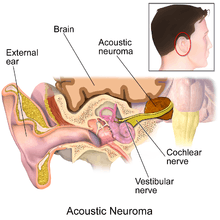

A vestibular schwannoma is a benign primary intracranial tumor of the myelin-forming cells of the vestibulocochlear nerve (8th cranial nerve). A type of schwannoma, this tumor arises from the Schwann cells responsible for the myelin sheath that helps keep peripheral nerves insulated.[1] Although it is commonly called an acoustic neuroma, this a misnomer for two reasons. First, the tumor usually arises from the vestibular division of the vestibulocochlear nerve, rather than the cochlear division. Second, it is derived from the schwann cells of the associated nerve, rather than the actual neurons (neuromas).

Acoustic neuromas (ARs), the common term for vestibular schwannomas, are neither 'acoustic' nor neuromas, since they do not arise from nerve tissue itself - ARs develop from an over production of non-neuronal glial (Schwann) cells that support and protect the vestibular (balance) portion of the vestibulocochlear nerve (cranial nerve VIII). ARs are slow-growing local, benign and non-invasive. Progression to malignancy in this kind of tumor is rare. They normally develop gradually over a period of years, expanding at their site of origin roughly 1–2 mm each year; however, up to 50% of such tumors do not grow at all, at least for many years after diagnosis. Tumor growth may be erratic, alternating between periods of relative dormancy or very slow growth and rapid growth. Tumors are typically described as small (less than 1.5 cm), medium (1.5 cm to 2.5 cm), large (2.5 cm to 4 cm),[9] or giant (greater than 4 cm). Tumors are described by a combination of their location and size. An intracanalicular tumor is small and in the internal auditory canal. A cisternal tumor extends outside the auditory canal. A compressive tumor infringes upon the cerebellum or brainstem. Very large tumors may obstruct cerebrospinal fluid drainage.

The tumor may develop within the auditory canal, where the vestibulocochlear nerve which supplies the inner ear penetrates the skull (intracanalicular neuroma) or outside the canal (extra-canalicular neuroma). The vestibulocochlear nerve has two components, the auditory and vestibular portions. Most schwannomas start out as intracanalicular, and growth compresses the nerve against the bony canal, so the first symptoms of the tumor are unilateral sensorineural hearing loss or distubances in balance. It may also compress the labyrinthine artery (main artery supplying the vestibular apparatus and cochlea of the inner ear) which passes through the auditory canal, resulting in ischemia or infarction ('heart attack' of the ear, resulting in death of the supplied tissue).

As intracanalicular tumors grow, they tend to expand into the cerebellopontine angle (CPA), leading to their characteristic "ice-cream-cone like" appearance on a radiograph. When the tumor expands extracanalicularly, the growth rate often increases, since it is no longer confined by the bony auditory canal. As the schwannoma expands into the CPA, it may infringe on cranial nerve V (controls facial sensation, chewing and swallowing) and cranial nerve VII (controls facial expression and taste). Cranial nerve VIII, along with these two nerves, also passes through the CPA, so more serious or complete hearing loss and episodes of vertigo may occur as the tumor infringes on it there.